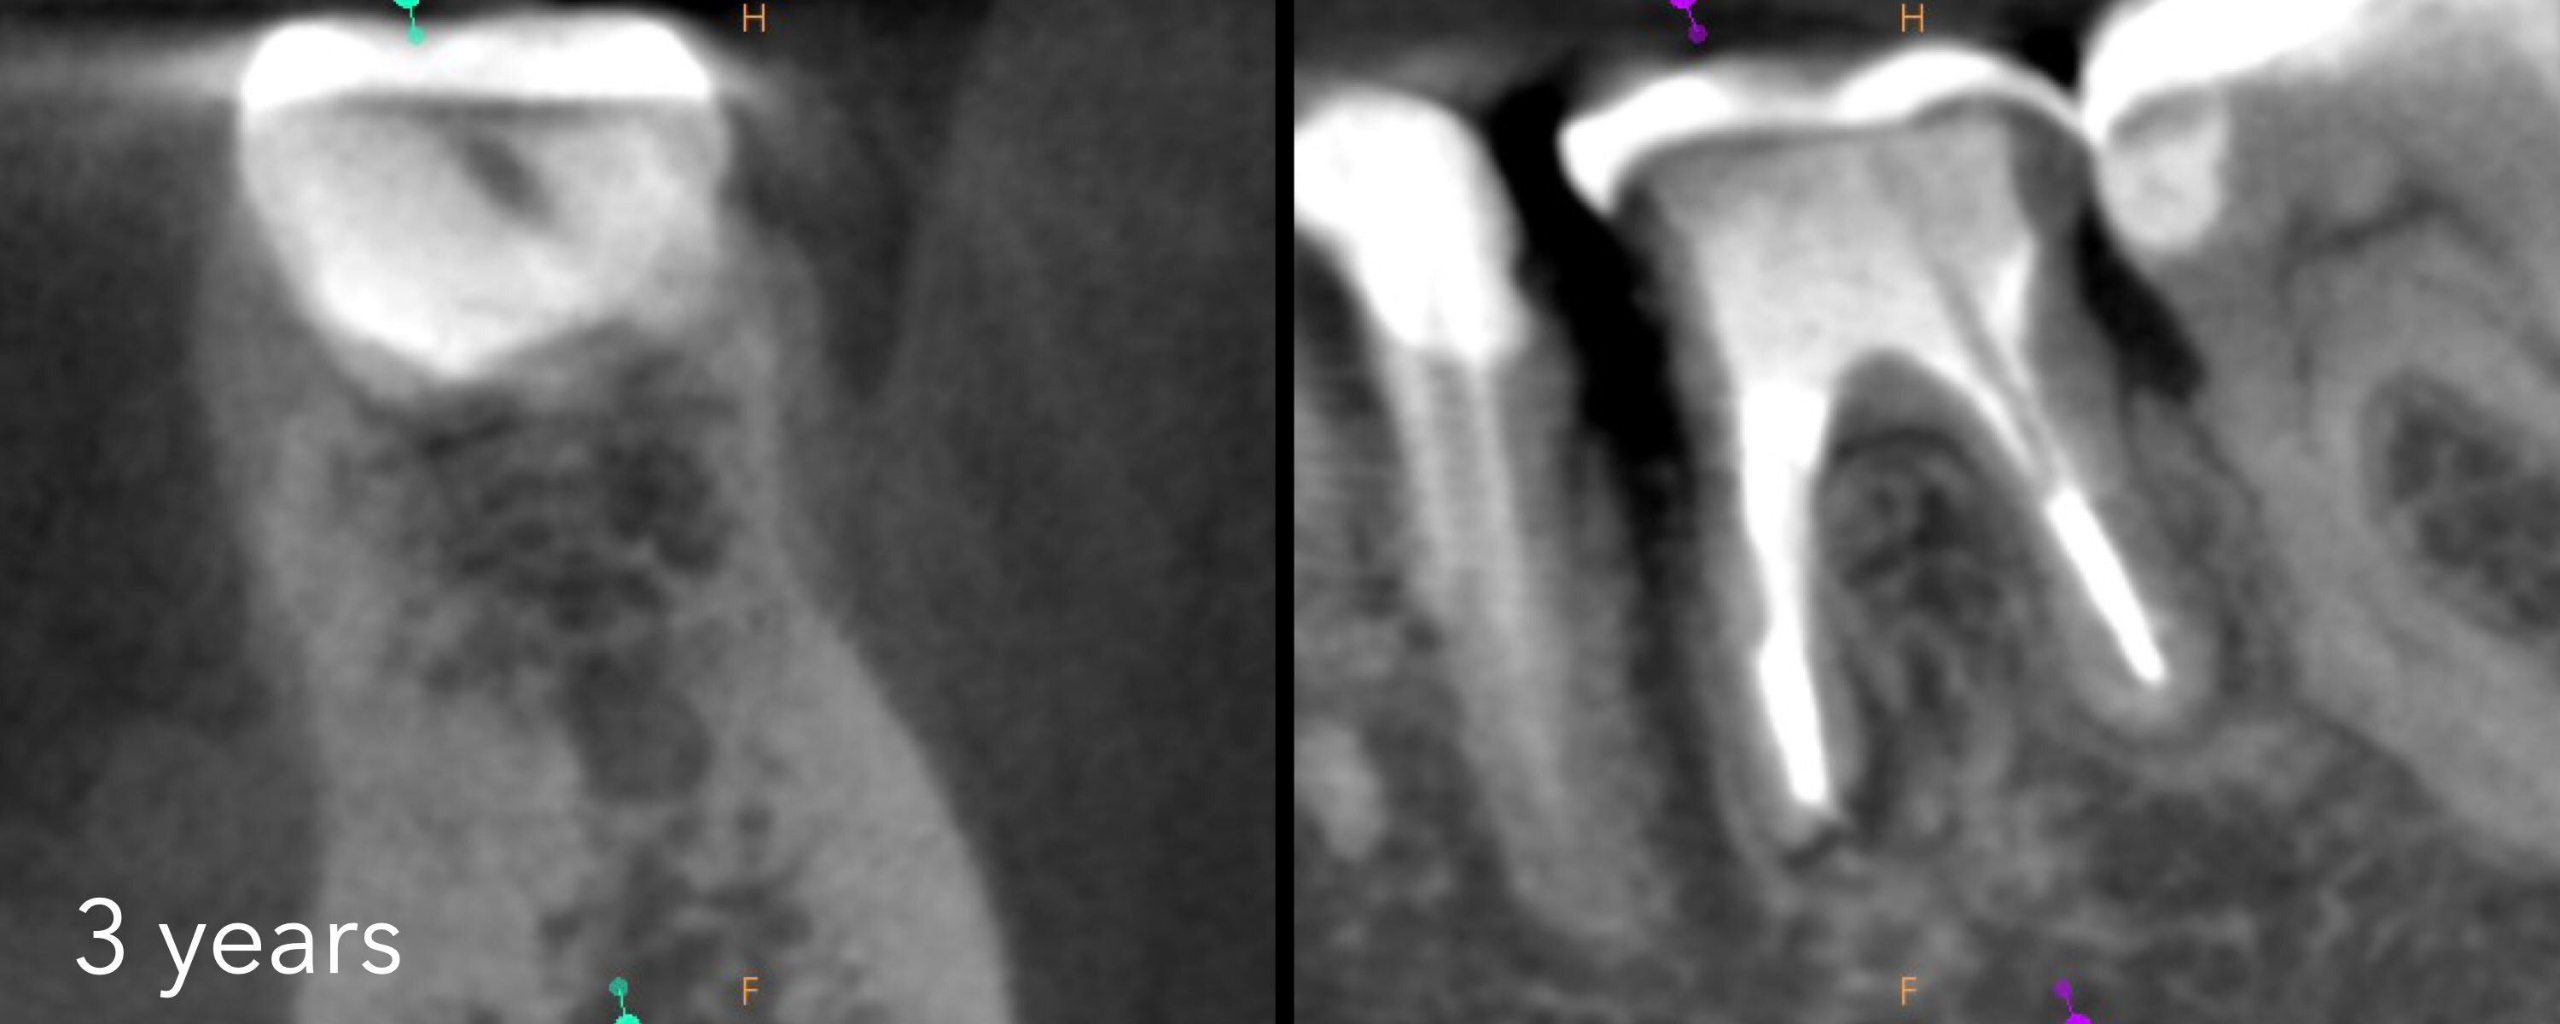

In this webinar, Dr. Ash Mark will tackle three of the most challenging endodontic complications: file fracture, perforation, and impassable ledged canals.

Attendees will learn practical, step-by-step strategies to overcome these obstacles with confidence and predictability.

This lecture emphasizes simple and repeatable techniques designed to streamline clinical workflows and ensure consistent, successful outcomes.